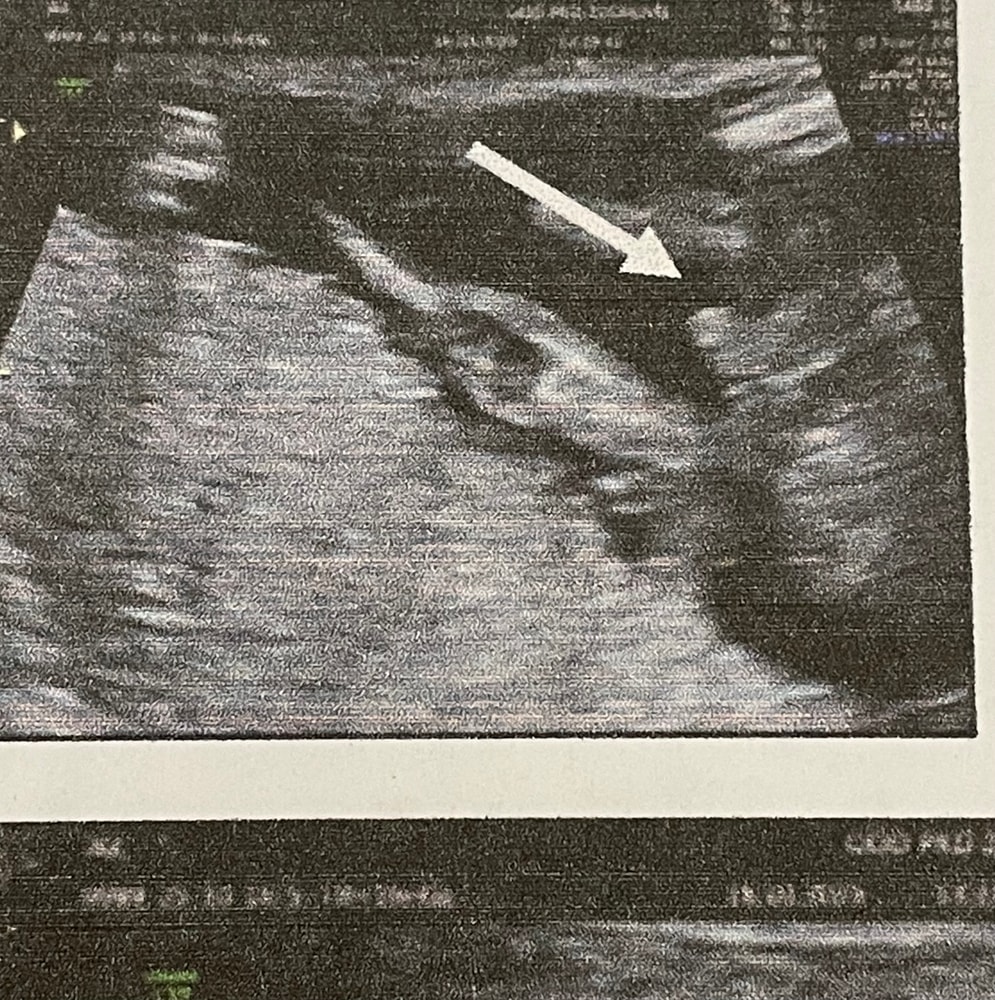

Пол малышаМамочки,нужен внимательный «опытный» взгляд) Что вы видите?)В 16 недель на УЗИ врач увидела мальчика. А теперь я читаю,что многим неверно определяют пол на этом сроке. Ну и все, я теперь загоняюсь,что вдруг на фото пуповина.А до второго скрининга еще почти три недели. Одно фото от врача,другое скрин с видео.

Ну по вашим снимкам узист должен быть слепой , чтобы увидеть тут девочку , и нет это не пуповина … у девочек в 15-16 недель между ножек уже четкое кофейное зернышко и ничего не торчит там , ракурс у вас удачный … на таком сроке наверно перепутать могут только на допотопном аппарате в глухой деревушке 😬🙈